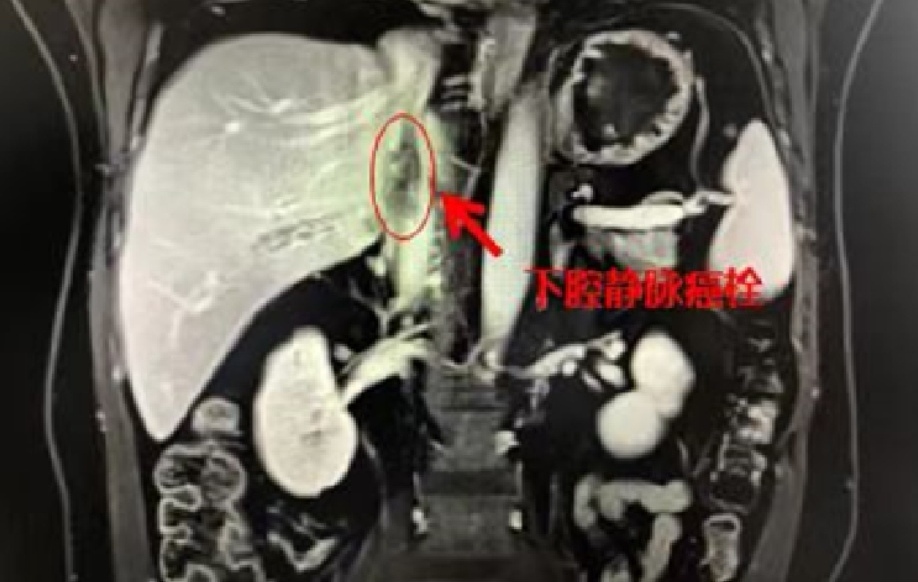

马先生家住广州花都,身体平时还算硬朗,没想到在一次普通的体检中却发现他已被肿瘤“击中”。中肿肝脏外科副主任李斌奎主任医师接诊后,综合影像检查结果,确诊马先生为肝右叶巨大肝癌,肿瘤直径超过10厘米,肝癌的血标志物甲胎蛋白超过18000纳克/毫升。由于肿瘤位置特殊、体积较大,癌细胞沿着肝脏血管蔓延,已经侵蚀到了下腔静脉形成了一条粗大的癌栓。

下腔静脉收集下半身的静脉血回右心房,是人体最大的一条静脉干,下腔静脉癌栓就意味着癌细胞直接“堵住”了生命要道。

下腔静脉癌栓形成